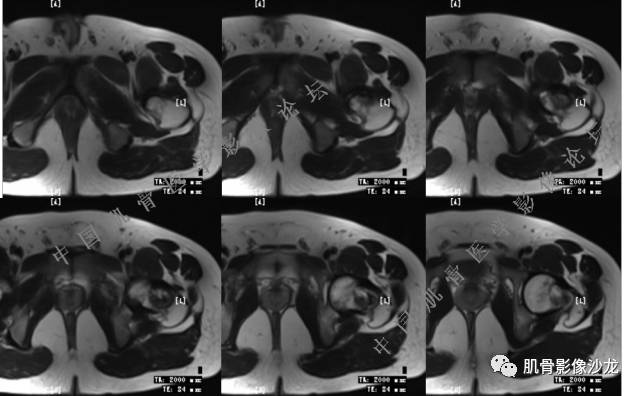

主诉:右大腿疼痛、活动受限20天

现病史:患者于20天前无明显诱因出现右下肢疼痛,活动受限,疼痛呈阵发性,活动后加重。自行口服止痛药芬必得,效果不佳,至当地医院治疗,检查发现右侧股骨近端病变。遂来诊

葛英霖 20:30 原发或继发动脉瘤样骨囊肿,继发于巨细胞瘤,软骨母,纤维组织细胞瘤,骨母等等

向以四 20:30 软骨母合并ABC,

医影在线 20:30 软骨母,/继发ABC

飞鹰行动 20:31 T2信号高,有软骨成分

Echo 20:32 T2确实有一块区域很亮 ,并有野液平

飞鹰行动 20:33 有侵袭性

飞鹰行动 20:35 骨皮质破坏,周围骨质异常信号

葛英霖 20:36 这不是良性病变

葛英霖 20:36 中间型可能性极大

葛英霖 20:37 明显侵蚀骨内膜啊,硬化边也不完整 (细箭头所示)

葛英霖 20:43 提不提也很明显继发了abc

葛英霖 20:44 是

葛英霖 20:46 明显的多囊状改变,液液平面